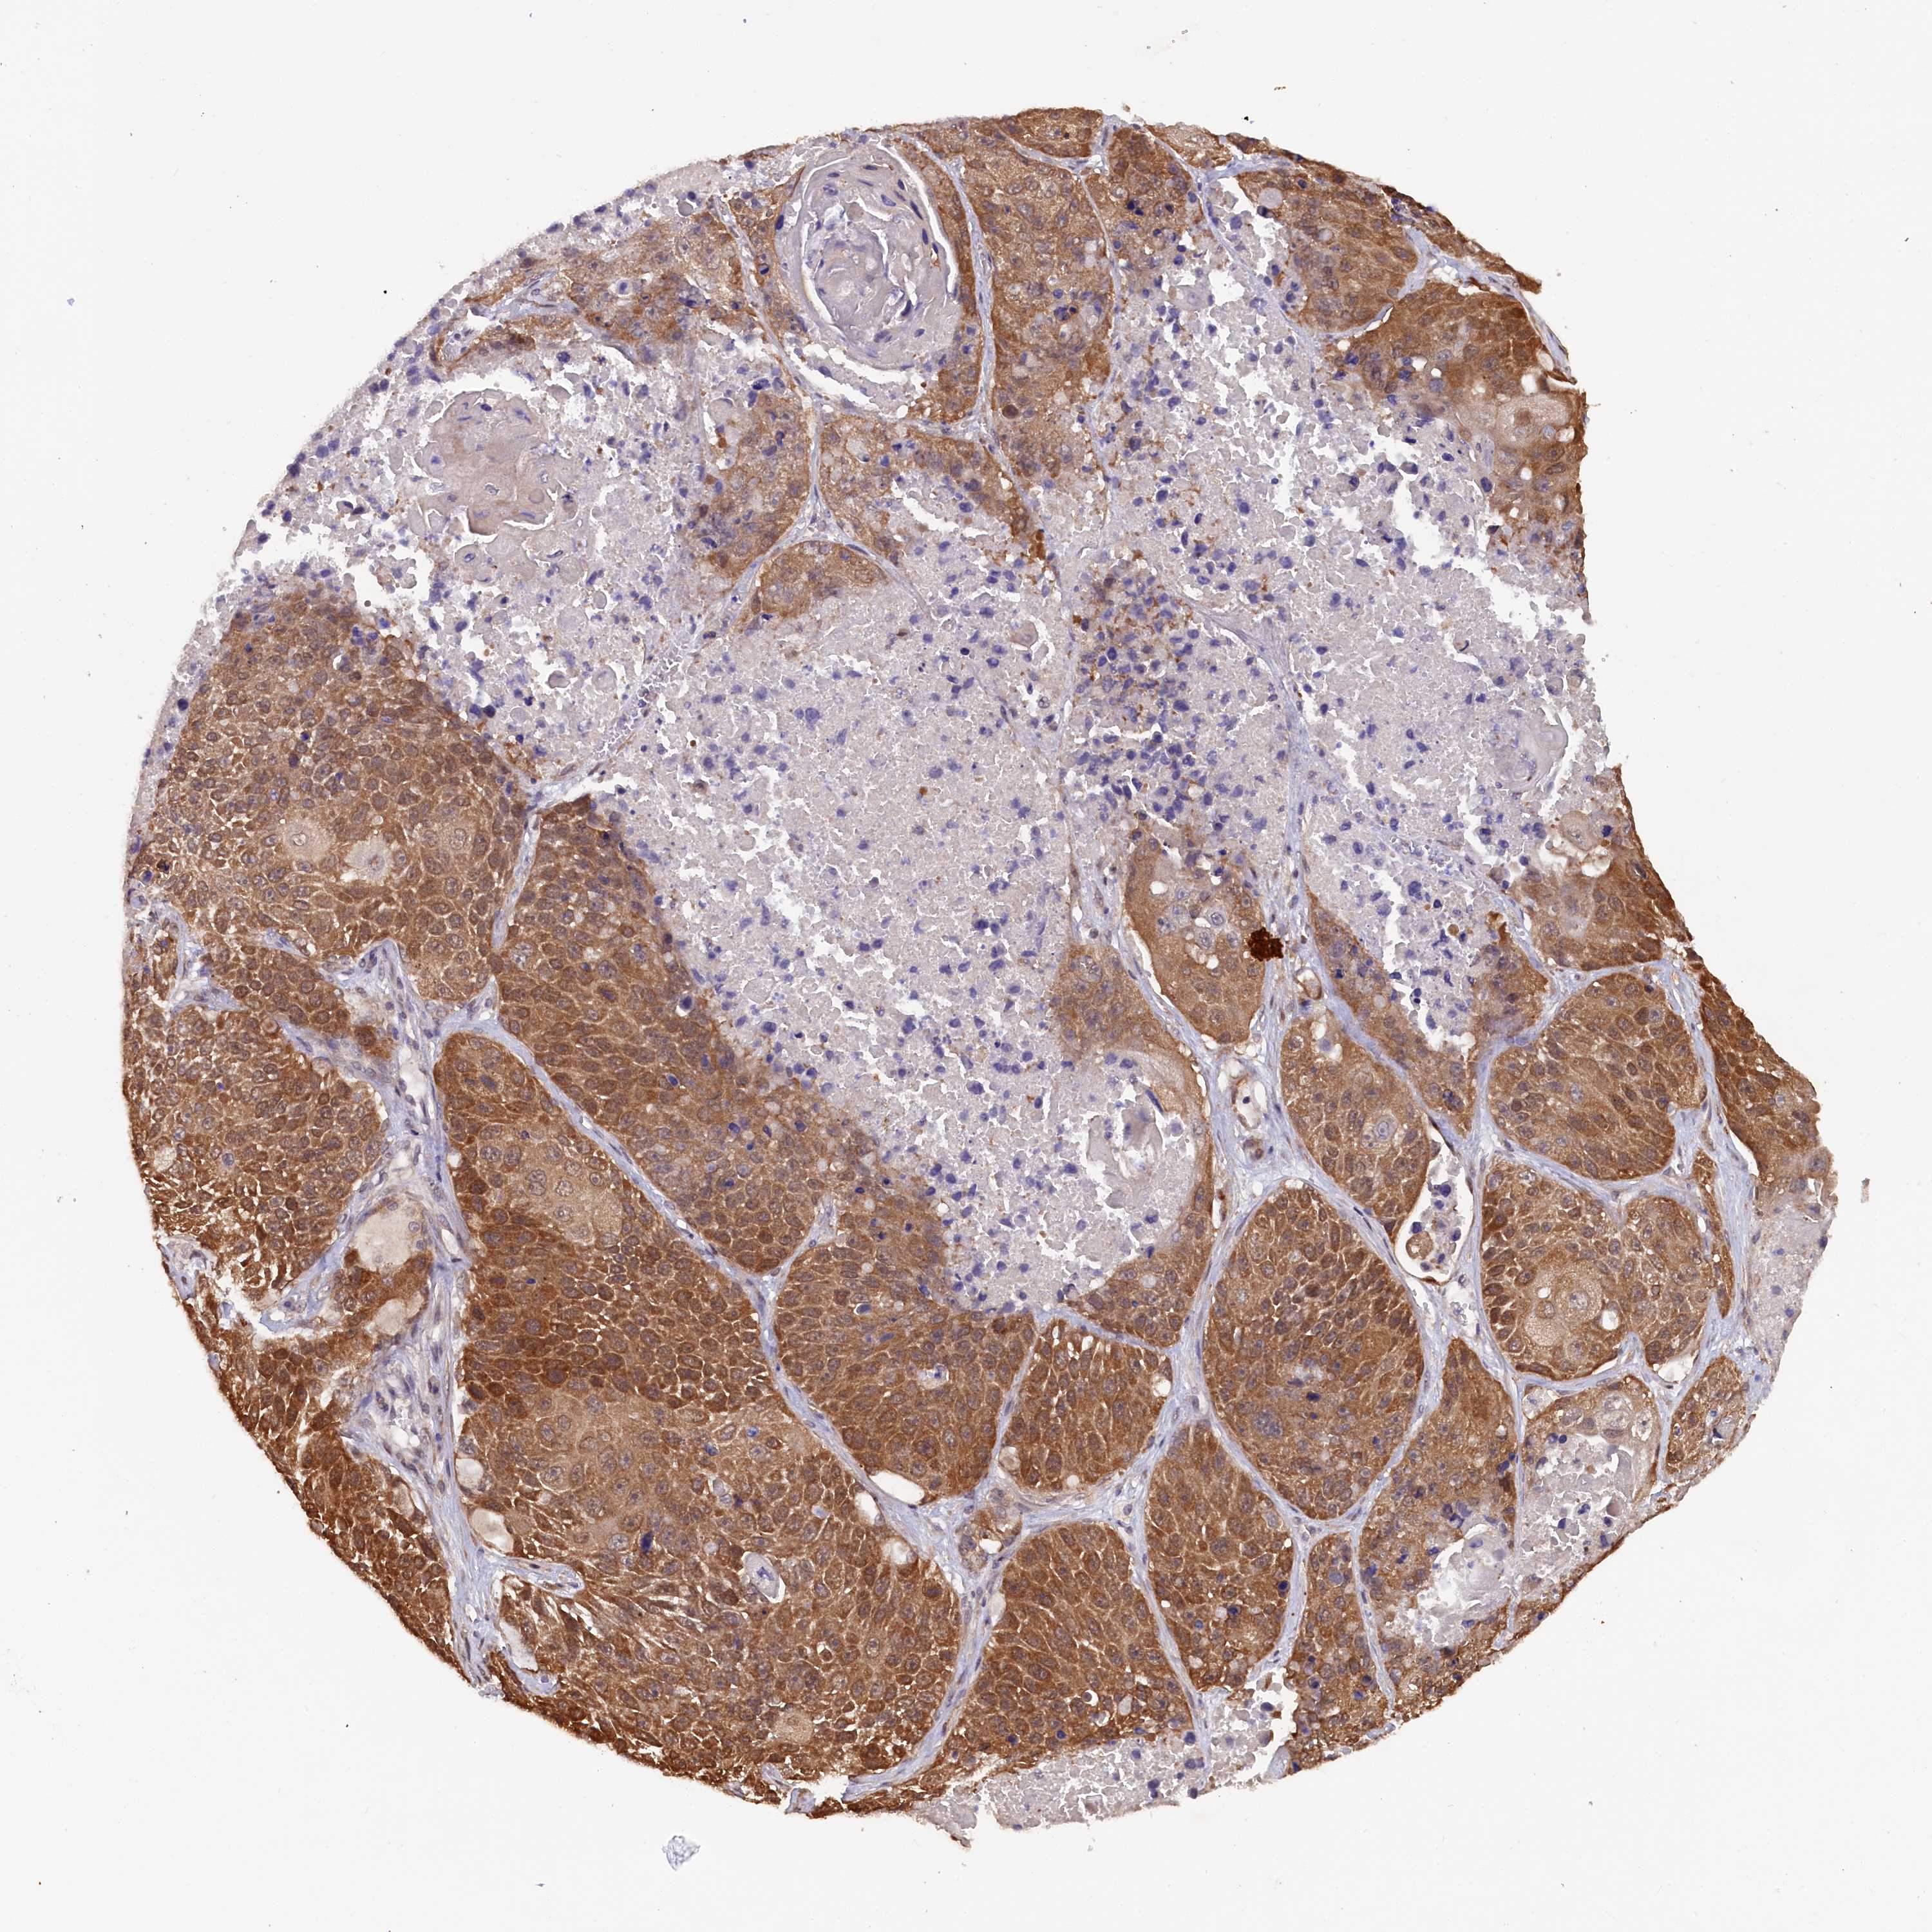

LUNG ADENOCARCINOMA (VALIDATION) - Interactive survival scatter ploti

The Survival Scatter plot shows the clinical status (i.e. dead or alive) for all individuals in the patient cohort, based on the same data that underlies the corresponding Kaplan-Meier plots. Patients that are alive at last time for follow-up are shown in blue and patients who have died during the study are shown in red.

The x-axis shows the expression levels (FPKM) of the investigated gene in the tumor tissue at the time of diagnosis. The y-axis shows the follow-up time after diagnosis (years). Both axes are complimented with kernel density curves demonstrating the data density over the axes. The top density plot shows the expression levels (FPKM) distribution among dead (red) and alive patients (blue). The right density plot shows the data density of the survived years of dead patients with high and low expression levels respectively, stratified using the cutoff indicated by the vertical dashed line through the Survival Scatter plot. This cutoff is automatically defined based on the FPKM cutoff that minimizes the p-score. The cutoff can be changed by dragging the vertical line or by entering a cutoff value in the square labeled "Current cut-off".

Under the Survival Scatter plot the p-score landscape (black curve; left axis) is shown together with dead median separation (red curve; right axis). Dead median separation is the difference in median mRNA expression between patients who have died with high and low expression, respectively. It is calculated as follows: median FPKM expression of dead patients with high expression - median FPKM expression of dead patients with low expression. This is intended to aid the user in visually exploring custom cutoffs and the associated p-scores and dead median separation.

Individual patient data is displayed and can be filtered by clicking on one or more of the category buttons on the top of the page. Categories describing expression level and patient information include: high, low, alive, dead, female, male and tumor stages. The scale of the x-axis can be toggled between linear and log-scale by clicking on the "x log" button. Mouse-over function shows TCGA ID, patient information and mRNA expression (FPKM) for each patient.

& Survival analysisi

Kaplan-Meier plots summarize results from analysis of correlation between mRNA expression level and patient survival. Patients were divided based on level of expression into one of the two groups "low" (under cut off) or "high" (over cut off). X-axis shows time for survival (years) and y-axis shows the probability of survival, where 1.0 corresponds to 100 percent.

JPT2 is not prognostic in Lung Adenocarcinoma (validation)

Best expression cut offi

Based on the FPKM value of each gene, patients were classified into two groups and association between prognosis (survival) and gene expression (FPKM) was examined. The best expression cut-off refers the FPKM value that yields maximal difference with regard to survival between the two groups at the lowest log-rank P-value. Best expression cut-off was selected based on survival analysis .

When clicking on this number, the vertical dashed line indicating cut-off, the interactive survival plot, and the Kaplan-Meier curve will be adjusted to show results based on the best expression cut-off.

: 57.3

P scorei

Log-rank P value for Kaplan-Meier plot showing results from analysis of correlation between mRNA expression level and patient survival.

N/A

Average pTPM 74.7

Number of samples 105